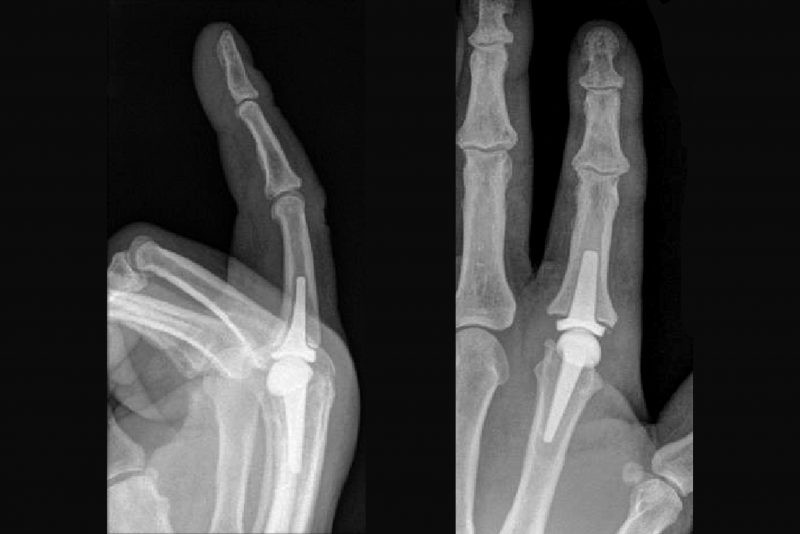

Figure 2. Illustration of a pyrocarbon and a silastic metacarpophalangeal (MCP) joint replacement in the finger.

Figure 3. Example of a pyrocarbon joint implant used in selected hand joints.

Figure 4. X-ray views of pyrocarbon joint replacements in small finger joints.